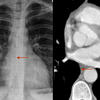

PA angio

Fig 1